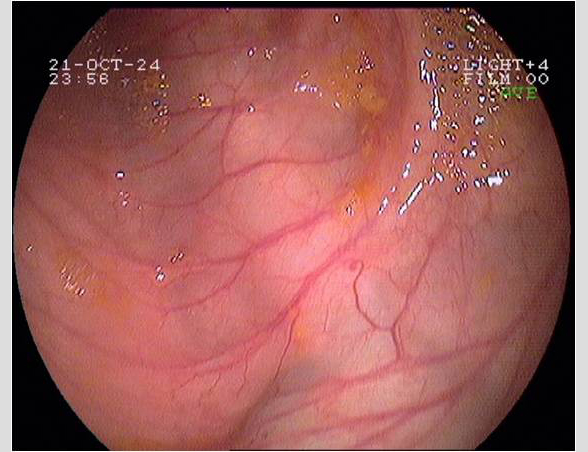

Imágenes tomadas durante la endoscopia digestiva alta y la colonoscopia. Se aprecia una mucosa de aspecto y vascularización normal, sin lesiones visibles. Se progresa con el colonoscopio hasta el íleon. Todo resulta macroscópicamente normal. Se toman biopsias de todos los segmentos explorados.

La endoscopia es el método de elección para el diagnóstico y seguimiento de la EII. Permite una visión macroscópica de la mucosa intestinal y la toma de múltiples biopsias para el estudio histológico.

Realizamos una endoscopia digestiva alta y una colonoscopia a la paciente con toma de biopsias, obteniendo el informe de Anatomía patológica.